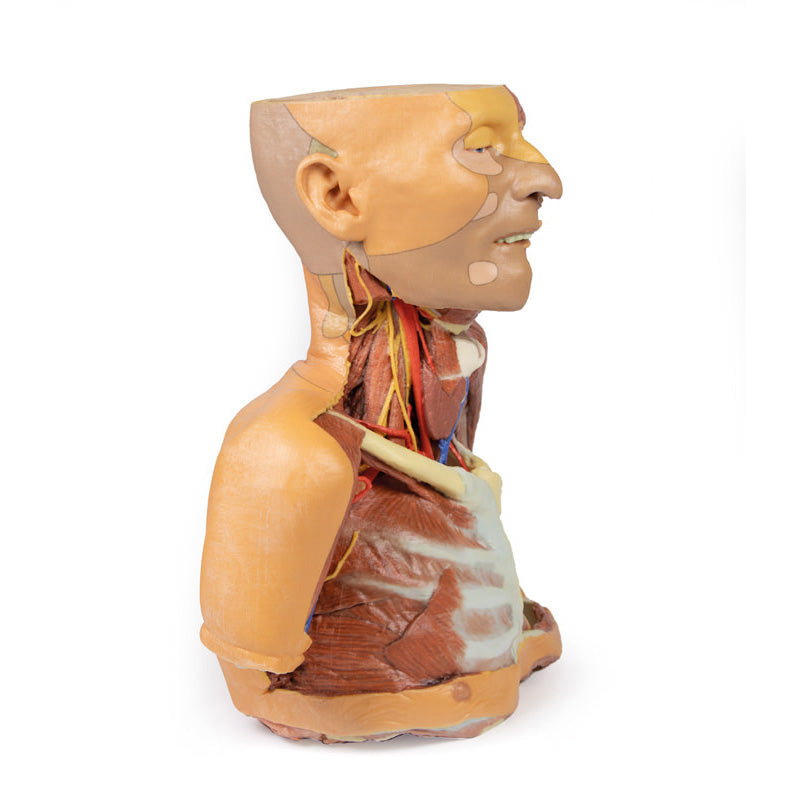

The head and neck of the specimen provides views of both superficial and deep structures in the region. The calotte has been removed ~2cm superior to the orbits to expose the brain in relation to the endocranial cavity. The transverse section through the cerebrum demonstrates the relation of the grey matter cortex to the white matter medulla, as well as the lateral ventricles with a small amount of choroid plexus visible in the base of both spaces. The skin and superficial fascia on the right side has been retained and false-coloured to display the angiosomes of the face and posterior neck. On the left side, the superficial tissues have been dissected to expose the muscles of facial expression, muscles of mastication, and deeper structures of the infratemporal fossa including the lingual nerve, terminal branches of the external carotid artery into the superficial temporal and maxillary arteries.

The carotid sheath has been opened on both sides of the neck, and the internal jugular veins and sternocleidomastoid muscles largely removed, to expose the pathway of the common carotid arteries, internal and external carotid arteries, and the vagus nerves. On the right side, the great auricular nerve ascends towards the face, while the hypoglossal nerve can be seen adjacent to the exposed stylohyoid ligament and supra- and infrahyoid muscles. A large thyroid gland is present bilaterally inferior to the thyroid cartilage, with a well-preserved superior thyroid artery and inferior thyroid vein on the right side and across the midline.

The clavicle has been partially removed on the left side of the specimen (medial to the origin of the deltoid) to expose the first rib and the insertion of anterior scalene muscle. The roots of the brachial plexus (C5-T1) can be seen forming the trunks posterior to this muscle but anterior to middle and posterior scalene muscles they emerge from the interscalene plane. While the subclavian vein has been removed, the subclavian artery is also seen passing behind the scalenus anterior. The transition of the subclavian artery to the axillary artery is exposed, as is its position relative to the cords of the brachial plexus (medial, lateral and posterior).

The head and neck of the specimen provides views of both superficial and deep structures in the region. The calotte has been removed ~2cm superior to the orbits to expose the brain in relation to the endocranial cavity. The transverse section through the cerebrum demonstrates the relation of the grey matter cortex to the white matter medulla, as well as the lateral ventricles with a small amount of choroid plexus visible in the base of both spaces. The skin and superficial fascia on the right side has been retained and false-coloured to display the angiosomes of the face and posterior neck. On the left side, the superficial tissues have been dissected to expose the muscles of facial expression, muscles of mastication, and deeper structures of the infratemporal fossa including the lingual nerve, terminal branches of the external carotid artery into the superficial temporal and maxillary arteries.

The carotid sheath has been opened on both sides of the neck, and the internal jugular veins and sternocleidomastoid muscles largely removed, to expose the pathway of the common carotid arteries, internal and external carotid arteries, and the vagus nerves. On the right side, the great auricular nerve ascends towards the face, while the hypoglossal nerve can be seen adjacent to the exposed stylohyoid ligament and supra- and infrahyoid muscles. A large thyroid gland is present bilaterally inferior to the thyroid cartilage, with a well-preserved superior thyroid artery and inferior thyroid vein on the right side and across the midline.

The clavicle has been partially removed on the left side of the specimen (medial to the origin of the deltoid) to expose the first rib and the insertion of anterior scalene muscle. The roots of the brachial plexus (C5-T1) can be seen forming the trunks posterior to this muscle but anterior to middle and posterior scalene muscles they emerge from the interscalene plane. While the subclavian vein has been removed, the subclavian artery is also seen passing behind the scalenus anterior. The transition of the subclavian artery to the axillary artery is exposed, as is its position relative to the cords of the brachial plexus (medial, lateral and posterior).